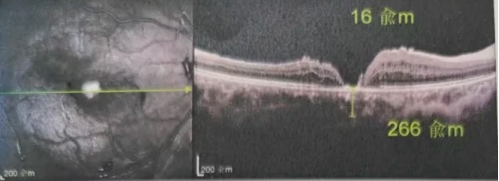

最讓吳爺爺難以置信的是:術后只需保持平躺24小時!第二天復查時,眼底鏡及OCT檢查清晰顯示——那個折磨了他大半年的大裂孔,竟然閉合了!且吳爺爺?shù)挠已垡暳τ辛嗣黠@的改善,術后3天已經(jīng)可以看到 0.15。